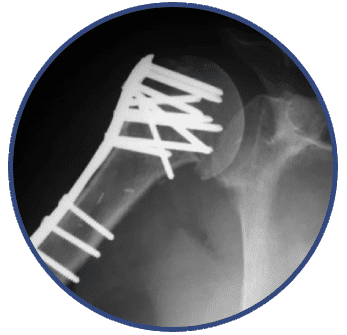

Tratamiento quirúrgico de fracturas

Cirugía para la reconstrucción de huesos fracturados.